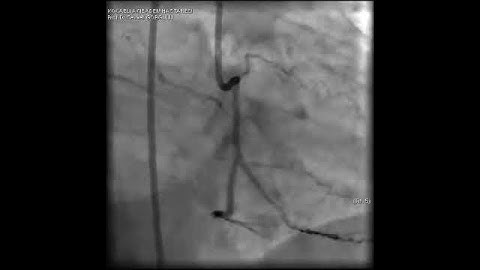

Complex PCI for RCA CTO with bifurcation at distal cap video 16